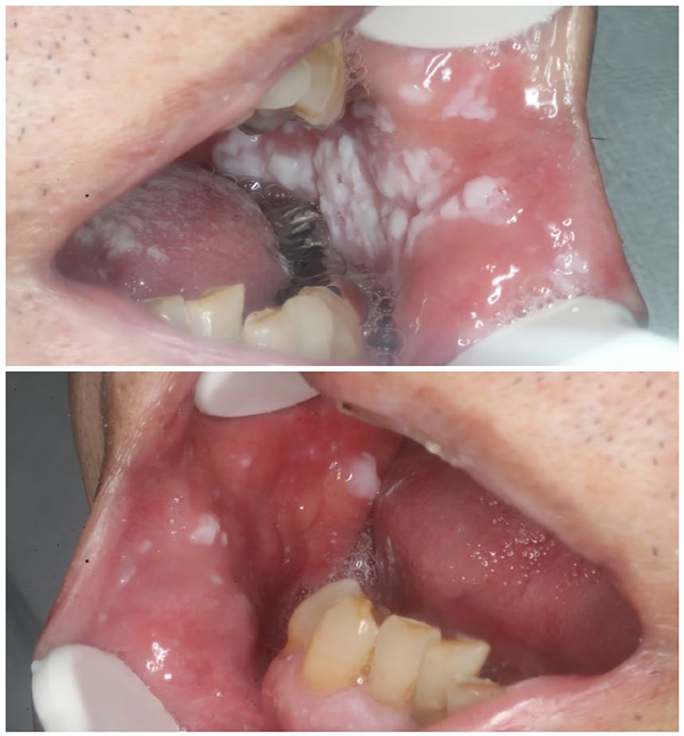

Lichen Planus

- Chronic inflammatory condition

- Reticular (lace-like) or erosive (ulcerative) lesions in the mouth

- T-cell-mediated autoimmune condition

Pemphigus Vulgaris

- Autoimmune blistering disease

- Oral ulcers often precede skin involvement

- Positive Nikolsky’s sign

Mucous Membrane Pemphigoid

- Chronic autoimmune blistering disorder involving oral mucosa

- Desquamative gingivitis common